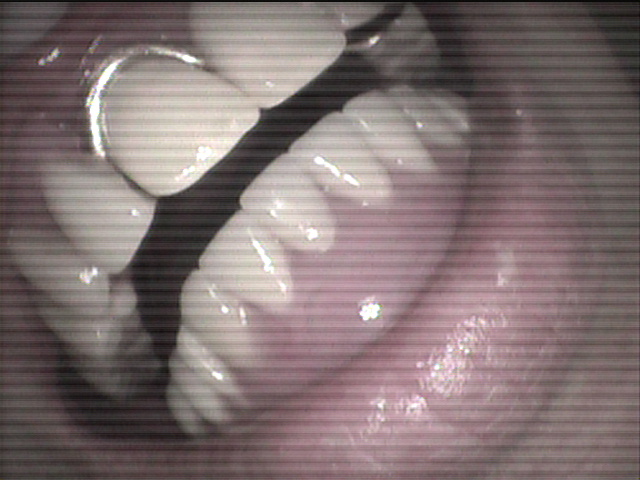

本日、出来上がりました自費の部分入れ歯ー下顎メタルプレートの症例です。

81歳の女性OUさんはとけも若々しいかたで、上下ともに、ぶぶん入れ歯ですが、今回は下顎の左右の奥歯のメタルプレートの入れ歯を新しく作りました。

自費によるメタルプレート義歯で、薄く丈夫な義歯として、とても舌感の良好な状態にすることができ、さらに自由な義歯の設計ができるため、残っているはにかける針金は白金加金で作成し、残存歯にやさしい設計となっており、舌に触れるバー部分はコバルトクロム合金で、丈夫に薄く作ってあります。

(参考代金;30万円)